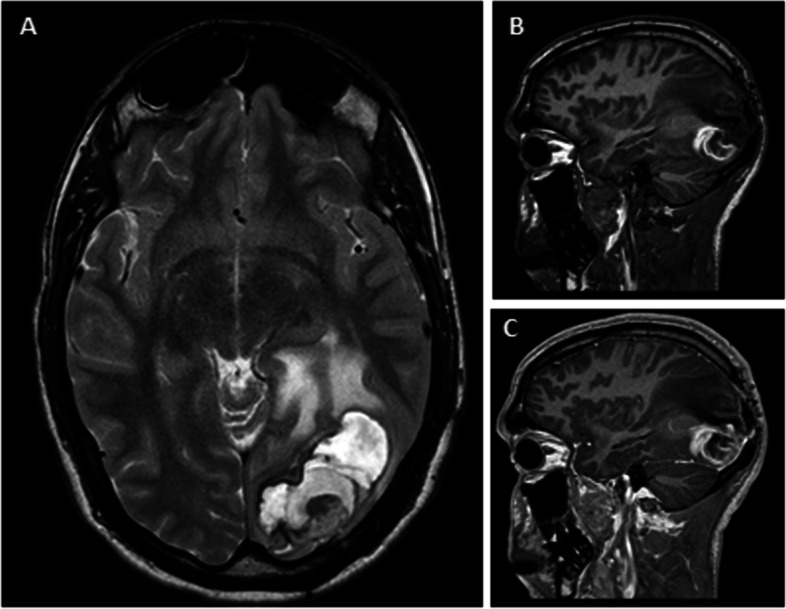

Case presentation: A case of a 28-year-old male with an increasing cyst formation (CF) appearing 10 years after SRS for AVM is presented. Despite surgical treatment, due to the incomplete resection of the angiomatous nodule, recurrence as a chronic encapsulated expanding hematoma (CEEH) occurred. This relapse required a second treatment, which could have been avoided if aggressive surgical treatment had been performed initially.

Conclusions: This case highlights the continuum between CF and CEEH, challenging existing confusion in the literature. Complete resection of the angiomatous nodule associated with CF is imperative for achieving resolution and preventing recurrence.